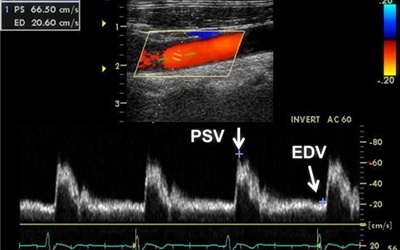

경동맥 초음파 검사는 목 부위에 위치한 경동맥의 상태를 실시간으로 확인할 수 있는 비침습적인 검사 방법입니다. 초음파를 이용하여 혈관 벽의 두께, 혈액의 흐름, 혈관 내 플라크(혈전)의 존재 여부 등을 파악할 수 있습니다. 마치 도로 위에 설치된 CCTV처럼, 혈관 속 상황을 안전하게 들여다보는 것이죠. 검사 과정은 간단하며, 통증이나 불편함이 거의 없어 누구나 부담 없이 받을 수 있습니다.

경동맥 협착은 경동맥 내부에 플라크가 쌓여 혈관이 좁아지는 질환입니다. 혈관이 좁아지면 뇌로 가는 혈류량이 감소하여 뇌졸중의 위험이 증가합니다. 경동맥 초음파 검사를 통해 협착의 정도를 정확하게 파악하고, 필요한 경우 약물 치료나 수술적 치료를 통해 뇌졸중을 예방할 수 있습니다.